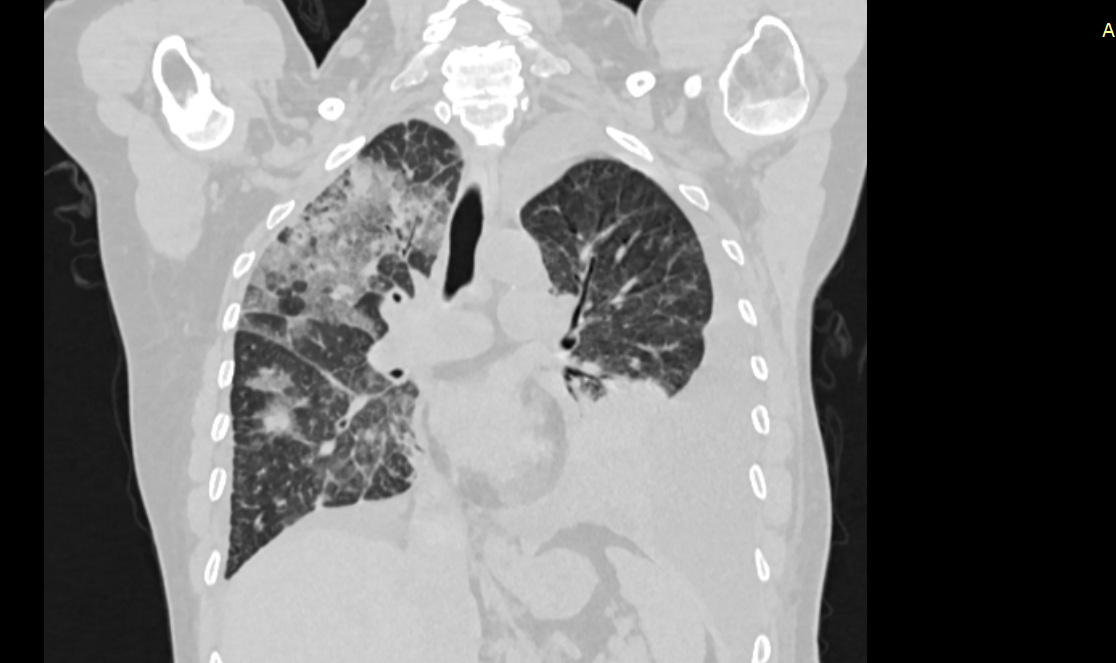

КТ органов грудной клетки, на снимке легко оценить степень поражения легочной ткани.